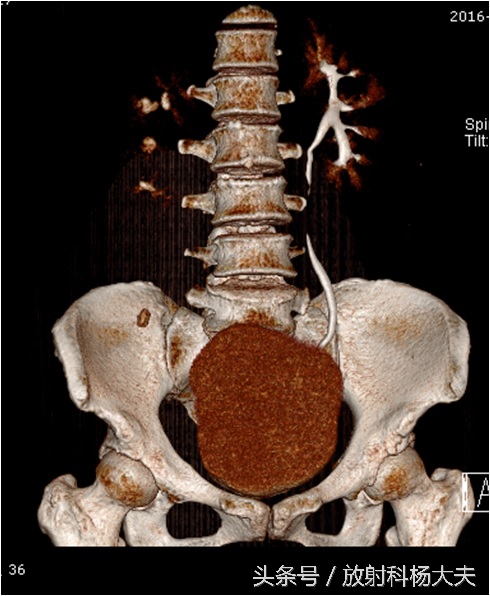

如下图就是宫颈的巨大肿瘤(圆圈所示),侵犯了右侧输尿管(红箭)。

引起了右肾积水。